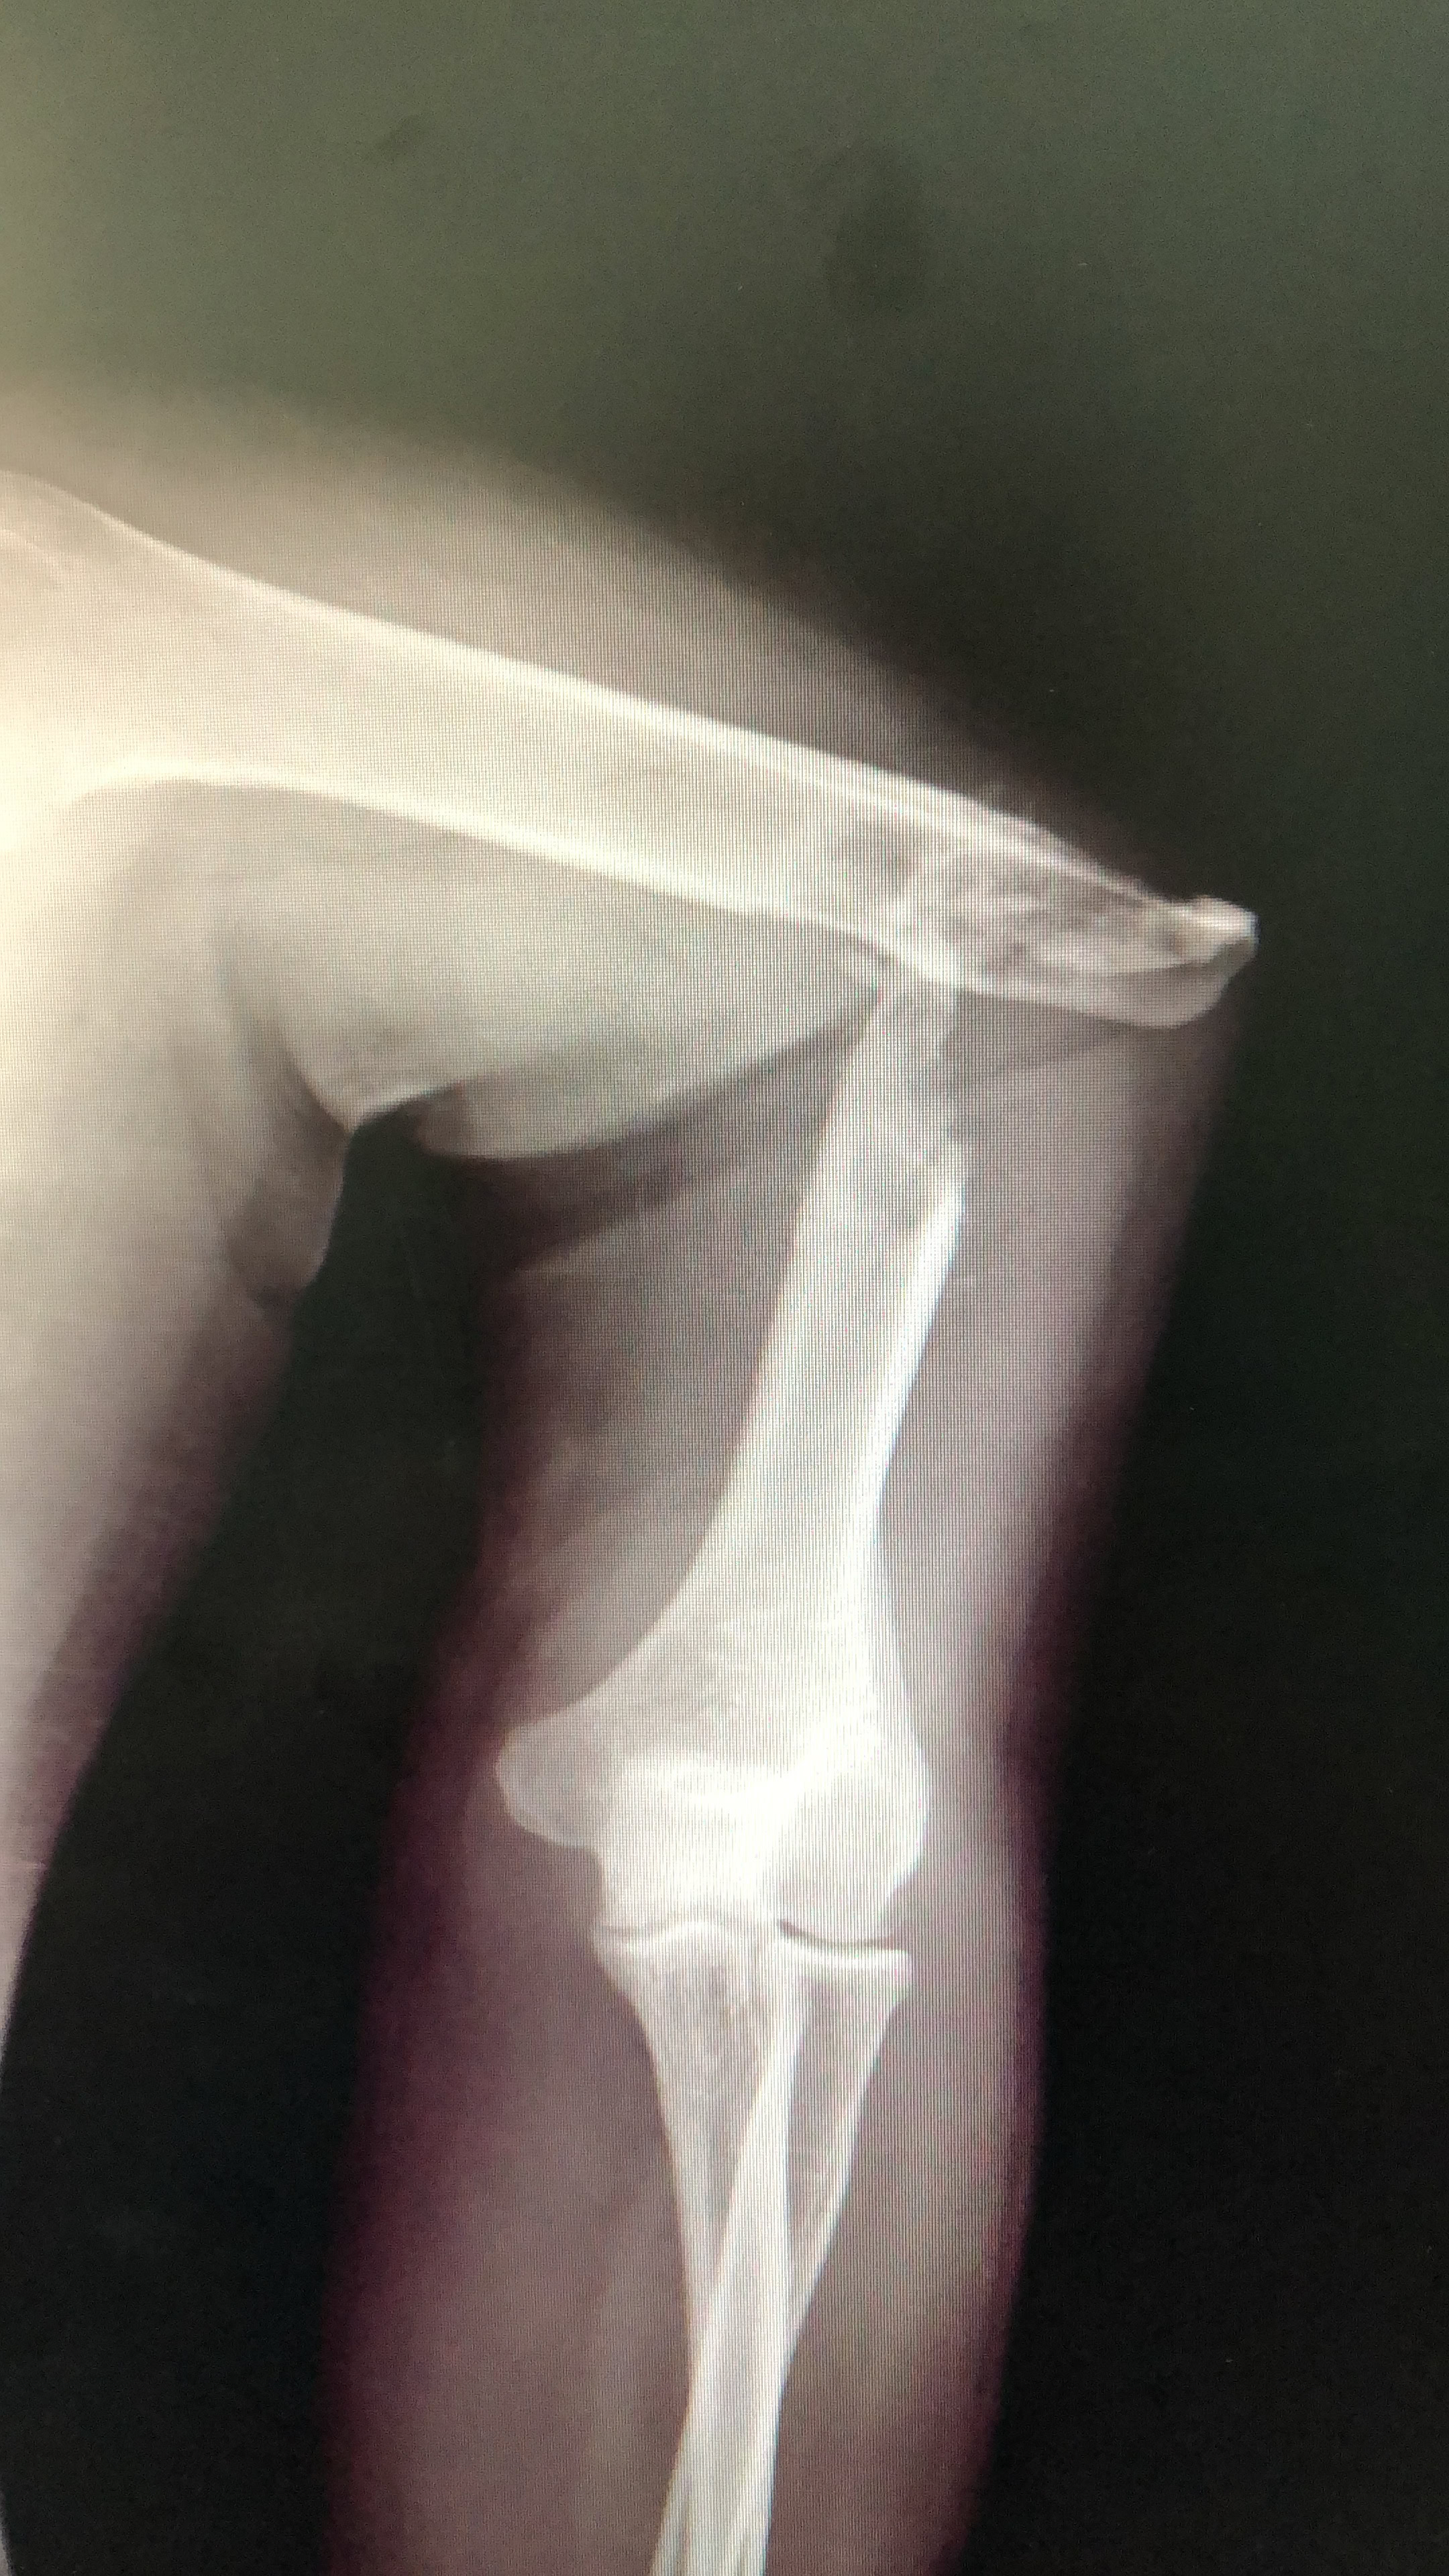

Y como traca final, el viernes por la tarde cuando íbamos a preparar ya las maletas para el viaje de vuelta, tuvimos  dos urgencias que requerían cirugía  de urgencia. Una artritis séptica de rodilla en un paciente de 21 años operado en otro centro hacía tiempo de un Girldestone por lo que suponemos fueron las complicaciones de una artritis séptica de cadera y con una osteomielitis del fémur. Y un paciente con luxación abierta de rodilla, fractura de cóndilo externo y fracturas abiertas de metatarsianos. Osea, toda la tarde del viernes trabajando.

La Dra. Zorita que viajaba por primera vez a nuestro Hospital en Dschang, ha visto patologías que en nuestro medio habitual en Europa son impensables. En la fotografía aparece junto a una paciente a la que le colocó un fijador externo por una fractura conminuta de pilón tibial abierta grado III B. También el Dr Soriano y el Dr Sotillo, que también era su primer viaje, pudieron actuar directamente en intervenciones que ya son muy raras para nosotros en el primer mundo.